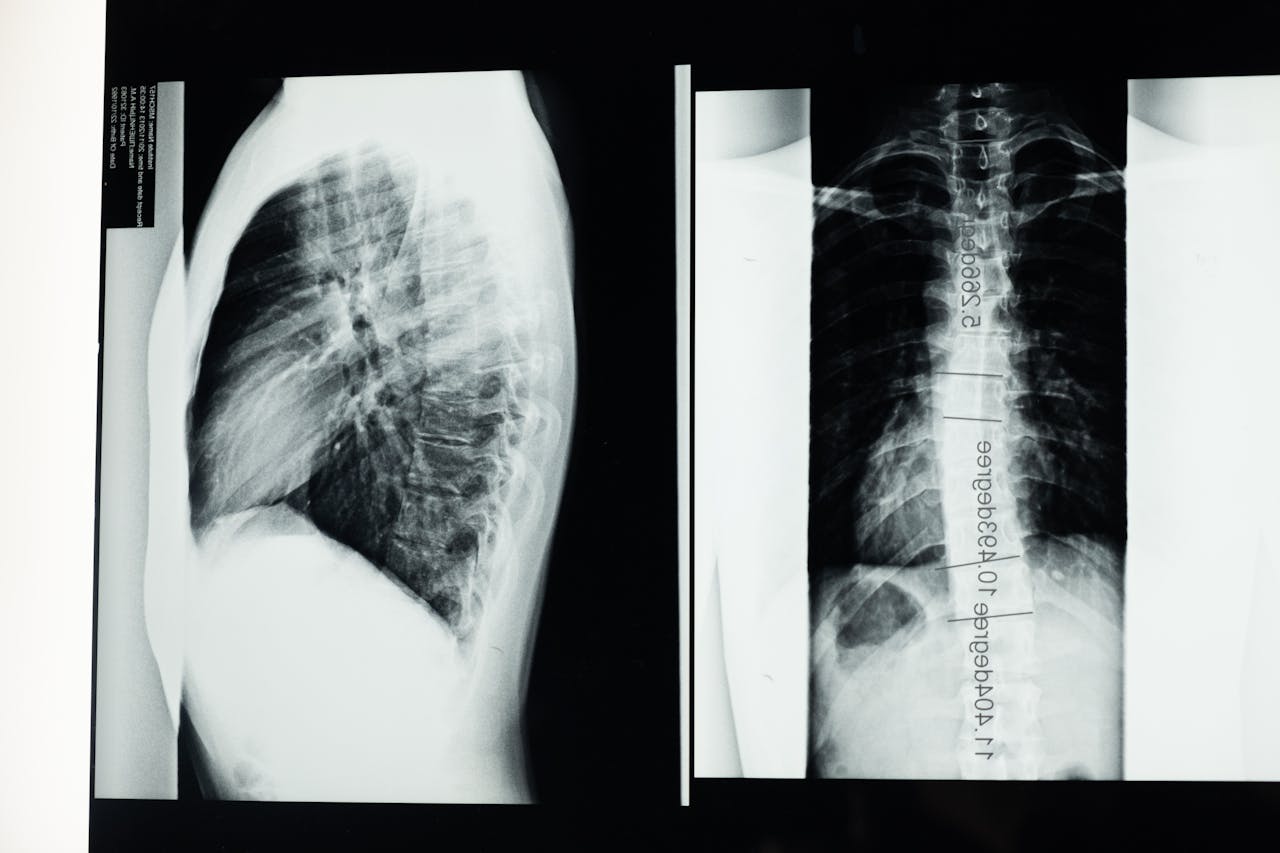

2. X-ray 촬영

✅ 병원에서 척추 전후·측면 X-ray 촬영으로 Cobb각(척추 만곡도) 측정.

✅ 만약 Cobb각이 10° 이상이면 척추측만증 진단, 20° 이상이면 보조기 착용이나 적극적인 치료 고려.